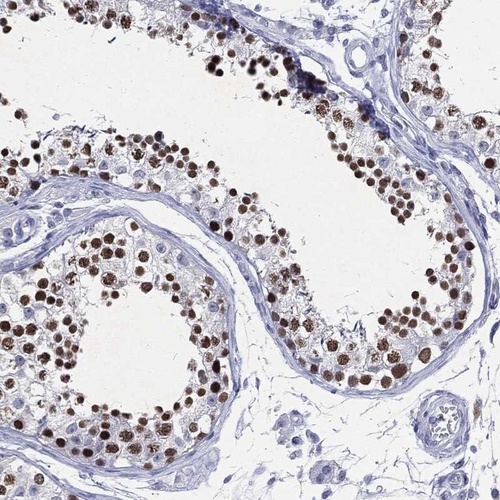

Immunohistochemical staining of human testis shows strong nuclear positivity in cells in seminiferous ducts.